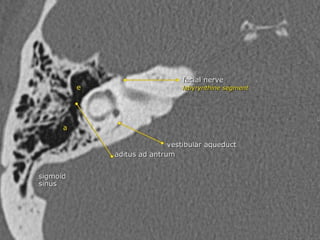

CT Temporal Bone Search Pattern with selected images :

Use both axial and coronal CT

images

Otic capsule:

•Superior semicircular canal (SCC)

•Posterior SCC (P)

•Lateral SCC (L)

•Vestibule (v)

•Aditus ad antrum (A)

•Cochlea

•Modiolus (mo)

•Basal turn (b)

•Middle turn (m)

•Apical turn

•IAC

•Facial n.

•labyrinthine segment (Fnl)

•geniculate segment

•tympanic segment

•Vestibular aqueduct